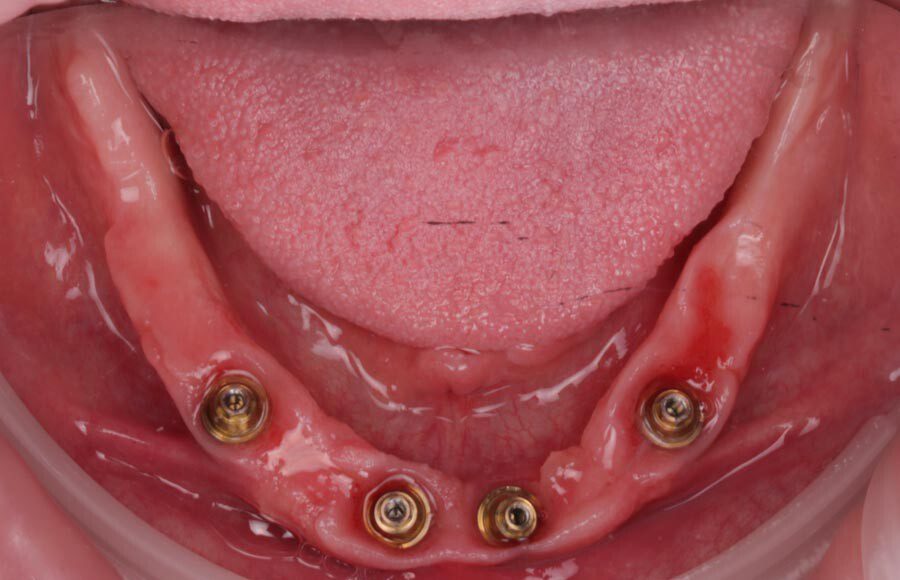

Smile GalleryImplant RestorationsImplant Dentures Post-op smiling 1 of 32 Pre-op close up smiling Pre-op lips retracted smiling Pre-op panoramic x-ray Implants in upper jaw (occlusal view) Implants in lower jaw (occlusal view) Panoramic x-ray of implants First set of try-ins – upper denture First set of try-ins – lower fixed provisional Delivered try-ins (lips retracted) Close adaptation to gums and appropriate emergence profile of lower fixed provisional Gum tissues have been molded by a convex provisional Delivered try-ins Second set of try-ins (lips retracted) Close adaptation to gums and appropriate emergence profile of second set of lower fixed provisional Delivered second try-ins Definitive restorations on casts (frontal view) Definitive restorations on cast (right side) Definitive restorations on cast (left side) Definitive upper overdenture (occlusal view) Definitive lower fixed titanium-acrylic hybrid restoration (occlusal view) Definitive lower fixed titanium-acrylic hybrid restoration (frontal view) Definitive lower fixed titanium-acrylic hybrid restoration (tissue side view) Healthy molded gum tissues on lower prior to delivery of lower fixed hybrid restoration Healthy gum tissues on upper prior to delivery of upper overdenture Definitive restorations (frontal, lips retracted) Definitive lower restoration (frontal) Definitive restorations (right side) Definitive restorations (left side) Definitive lower restoration (occlusal view) Definitive upper restoration (occlusal view) Post-op panoramic x-ray Post-op smiling